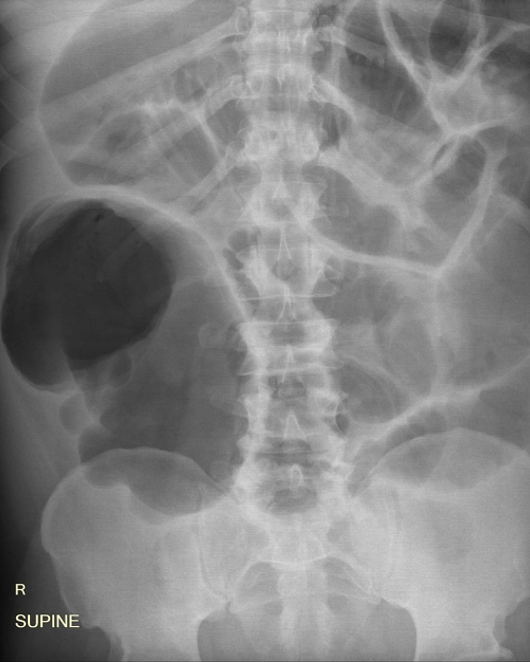

Answer: D) Sigmoid volvulus

Explanation: A coffee bean sign is shown which is an indication of a sigmoid volvulus, which is a condition where the sigmoid colon twists on its mesentery, causing obstruction.

C) is incorrect because caecal volvulus presents with the kidney bean sign.

E) is incorrect because small bowel obstruction shows dilatation of more than 3 cm and is characterised by the presence of plicae circularis/valvulae conniventes.